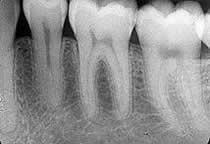

Dişlerin şekillerinde, yapılarında, renklerinde ve pozisyonlarında meydana gelen bozukluklar, estetik sorunlara yol açabilir. Dişi zayıflatan aşırı gelişmiş bir çürük veya dişe gelen bir darbe nedeni ile dişte oluşan madde kaybı, dolgu ile tedavi edilemeyebilir. Gelişimsel olarak dişin sürmemesi veya tıbbi nedenlerle dişin çekilmiş olması, ağızda dişsiz boşluklar meydana getirir. Bu boş alanlar, estetik bozuklukların yanı sıra,